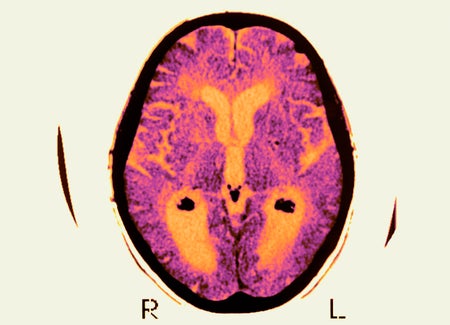

Controversial New Guidelines Would Diagnose Alzheimer’s before Symptoms Appear

According to expert recommendations, the diagnosis of Alzheimer’s can proceed by detecting the disease’s underlying biology—even before the onset of cognitive decline